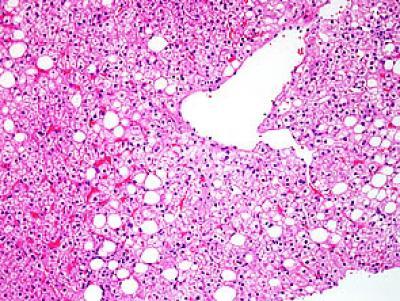

Two forms of nonalcoholic fatty liver disease (NAFLD) are depicted in these images of liver biopsies from adults, taken from this study. The first shows nonalcoholic fatty liver only.

(Photo Credit: Elizabeth Brunt, M.D., of Washington University in Saint Louis.)